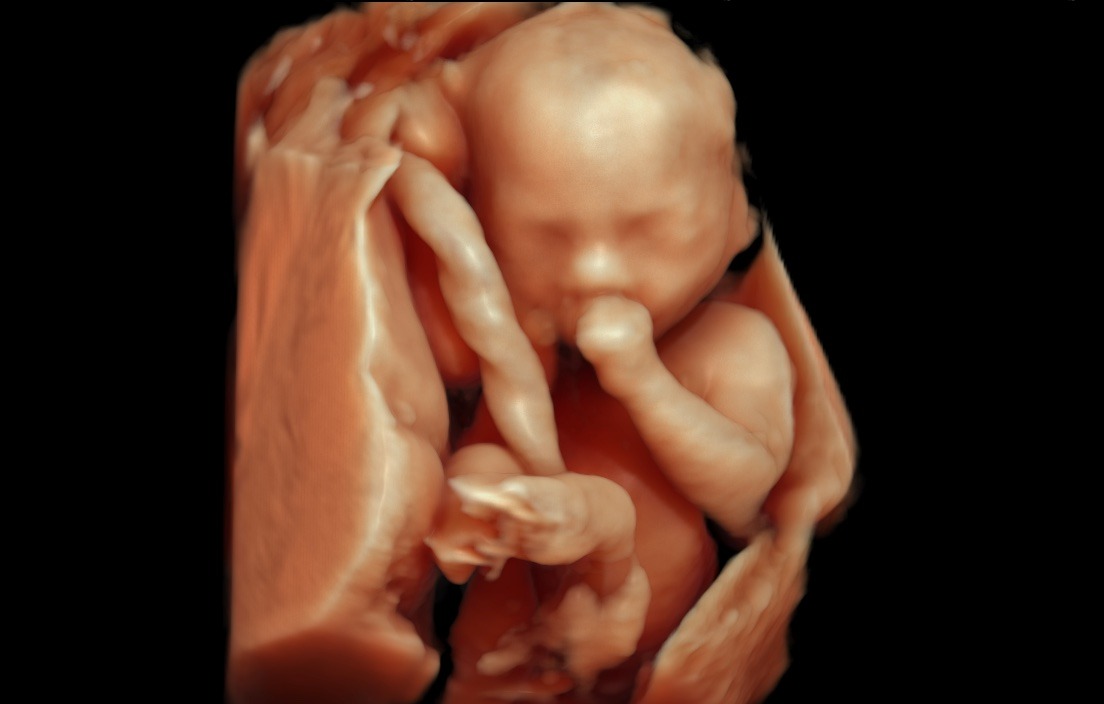

Naše klinika prenatální péče a genetiky nově disponuje nejvýkonnějším ultrazvukovým přístrojem na trhu –Voluson™ Expert 22 od GE Healthcare. Špičkový systém přináší zcela nový standard v oblasti prenatální diagnostiky.

„VolusonTM Expert 22 je přístrojem, který disponuje nejmodernějšími technologiemi pro zobrazování plodu ultrazvukem. Vysoká kvalita obrazu zaručuje mimořádně detailní a přesné zobrazení jednotlivých struktur plodu včetně jeho cévního zásobení. Tyto parametry nejen že zvyšují přesnost naší diagnostiky, ale hlavně posouvají naše možnosti záchytu vrozených vad do časnějších fází těhotenství. Kvalitní 3D/4D technologie zaručuje precizní posouzení prostorových vztahů. Bez její dostupnosti si dnes například nedokážeme představit cílené vyšetření mozku plodu a významně nám dokáže pomoci i v upřesnění celé řady dalších abnormálních nálezů. Takovéto přístrojové vybavení vnímáme jako nepodkročitelnou podmínku pro poskytování prenatální diagnostiky a té nejvyšší možné úrovni, “ prof. MUDr. Ivana Kacerovská Musilová, Ph.D. Odborný garant a gynekolog

„Jako první a dosud jediné zdravotnické zařízení v Pardubickém kraji můžeme našim klientkám nabídnout diagnostiku pomocí této špičkové technologie, kterou dosud využívají v ČR pouze jednotky specializovaných center. Díky Voluson™ Expert 22 jsme schopni detekovat i velmi diskrétní vady, které mnohdy může být velmi složité zobrazit na starších technologiích, dále tím zvyšujeme přesnost diagnostiky plodu. Naše pacientky mají jistotu, že dostávají tu nejlepší možnou péči s využitím nejmodernějších technologií dostupných v oblasti prenatální medicíny, “ dodává Ing. Ondřej Michalovský, výkonný ředitel společnosti